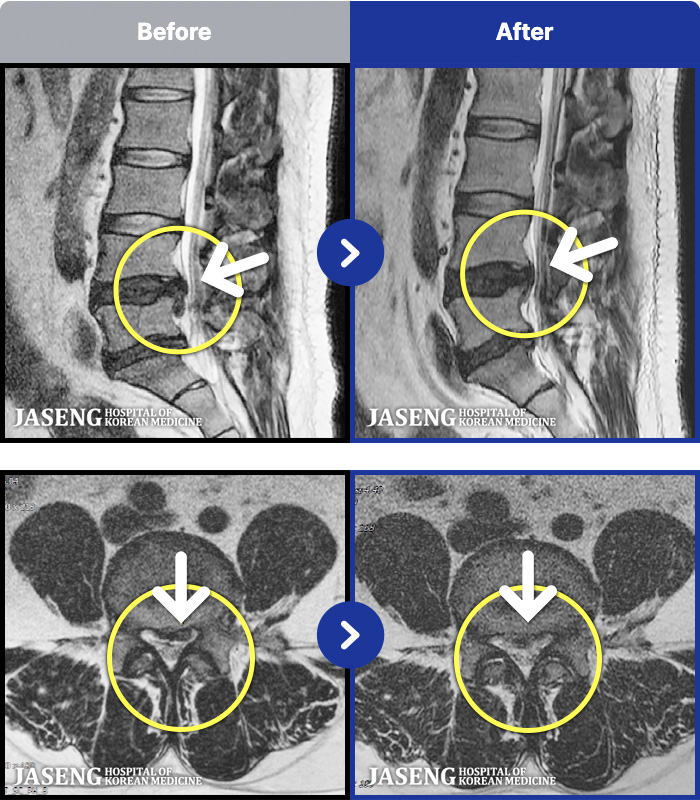

1,251 MRI ũ ʸ Ȯϼ.